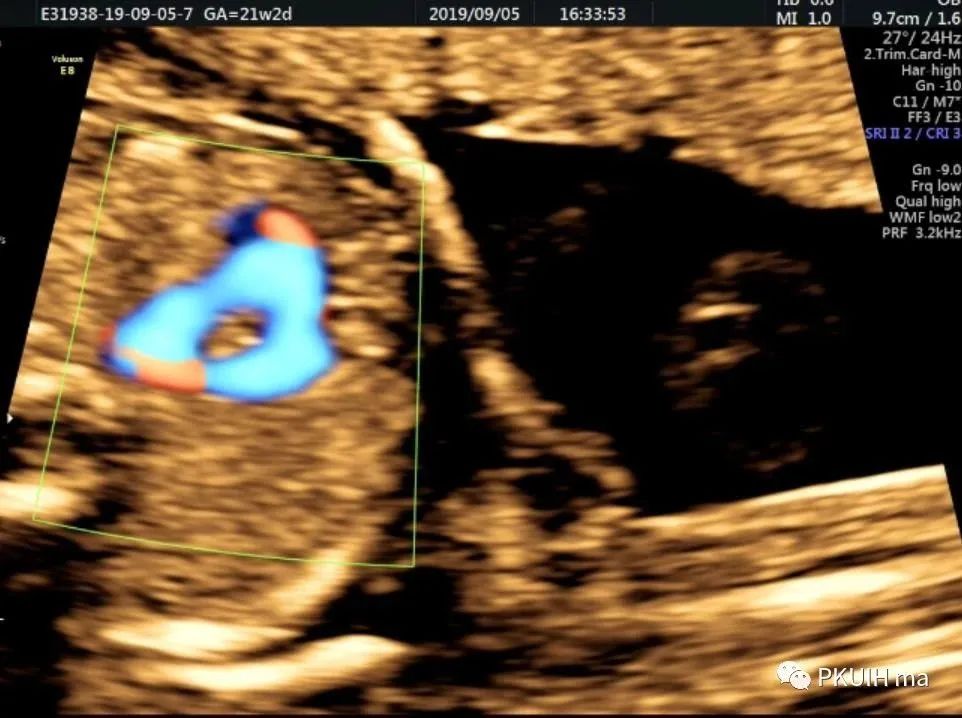

下面几张图都是右位主动脉弓、左动脉导管合并左锁骨下动脉迷走的病例,患儿出生后随访均无明显临床症状

主动脉弓走行于气管的右侧,与左位的动脉导管形成“U”型环(不完全血管环),包绕气管和食管。主动脉冠状切面可见左锁骨下动脉起自于主动脉弓降部,向左肩部走行。

右弓左导管是左位主动脉弓在左锁骨下动脉与左颈总动脉起始处之间退化,形成右弓,左位动脉导管存在于左锁骨下起源区域,右位动脉导管退化,从而形成左向右环绕气管的血管环。右位主动脉弓依次发出左颈总动脉、右颈总动脉、右锁骨下动脉及迷走的左锁骨下动脉。在个别情况下,左锁骨下动脉也可以通过Kommerell憩室的动脉管道直接起源于降主动脉。右位主动脉弓可以是复杂先心的一部分,也可以孤立存在。三血管气管切面是诊断右位主动脉弓的重要切面,结合血流显像可以鉴别右弓的三种类型。